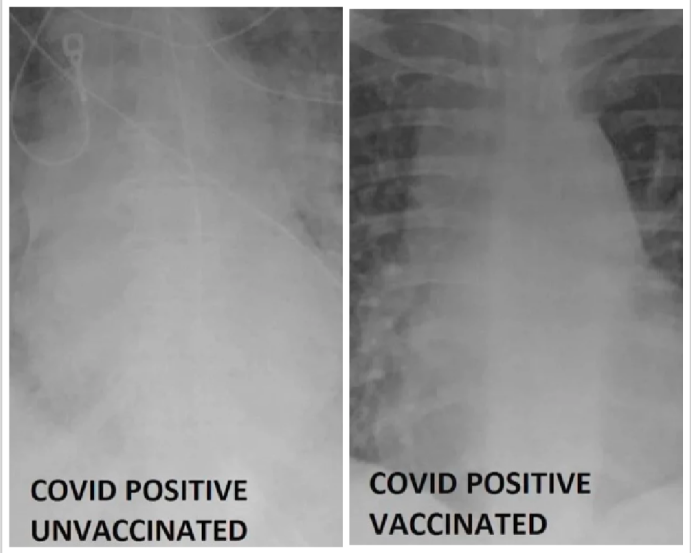

Vodja enote za intenzivno nego v univerzitetni bolnišnici St. Louis Gasan Kamel je predstavil sliko pacienta, ki se je cepil proti covidu-19, in tistim, ki se ni. Rentgenske slike je pokazal zato, da se ljudje začnejo bolj zavedati, zakaj je cepljenje izjemno pomembno za njihovo zdravje.

Dr. Gasan Kamel je svoje trditve podkrepil z nazornim dokazom. Na sliki pljuč pacienta, ki ni bil cepljen proti covid-19, se je po besedah strokovnjaka opazila bela pika oz. lisa. Ta lahko kaže na bakterijo, sluz ali izločke. Na podlagi slike je Kamel ugotovil, da bi ta pacient v primeru okužbe zagotovo potreboval kisik ali vsaj respirator.

Na drugi sliki lahko vidite pljuča cepljenega pacienta. Kot je pojasnil Kamel, so ta veliko čistejša. Na sliki so videti črna, ko so napolnjena z zrakom. Pri necepljenem bolniku je videti večinoma belo sliko, pri cepljenem pa je slika temnejša.

Pozitiven bolnik na covid-19, ki se ni cepil. Po sliki sodeč se bo njegovo življenje reševalo s respiratorjem. (Foto: Bolnišnica St. Lois, posnetek zaslona)

Ameriški zdravnik poudarja, da cepljene osebe, pozitivne na covid-19, pri bolnišničnem zdravljenju na splošno ne potrebujejo intenzivne nege, kot jo necepljene. Dodal je še, da morajo necepljenim bolnikom redno nuditi pripomočke za vzdrževanje življenja.

Pozitiven bolnik, ki se je cepil. Covid-19 bo prebolel z zelo blagimi simptomi. (Foto: Bolnišnica St. Lois, posnetek zaslona)

Kamel upa, da bodo slike ljudi prepričale, da se cepijo. “Če ne marate mask, vam tudi respirator zagotovo ne bo všeč,” je dejal.